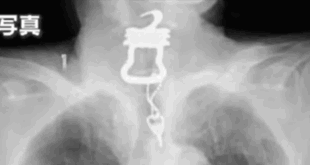

السجن لجرّاح بريطاني بتر ساقيه بدافع “الهوس”!

قررت محكمة التاج في مدينة ترورو البريطانية سجن جرّاح الأوعية الدموية نيل هوبر لمدة عامين وثمانية أشهر، بعد إدانته بالاحتيال على شركات التأمين وحيازة مواد إباحية متطرفة. وكشفت التحقيقات أن الطبيب البالغ من العمر 49 عاماً، والذي عمل لسنوات طويلة ضمن هيئة الصحة الوطنية البريطانية (NHS)، أجرى مئات عمليات البتر لمرضاه، قبل أن يتعمّد إلحاق أذى جسيم بساقيه باستخدام الثلج، ما دفع …